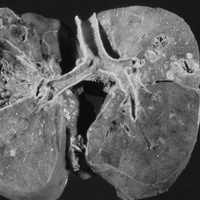

Инфекции мочевыводящих путей – состояние инфицирования мочевыводящего тракта микрофлорой, которая вызывает его воспаление.Различают инфекцию верхних (пиелонефрит) и нижних мочевых путей (цистит, простатит, уретрит) по наличию или отсутствию симптомов (симптоматическую или бессимптомную бак-териурию), по происхождению инфекции (внебольничную или нозокомиальную), осложненные и неосложненные.

Осложненные инфекции сопровождаются функциональными или анатомическими аномалиями верхних или нижних мочевых путей.